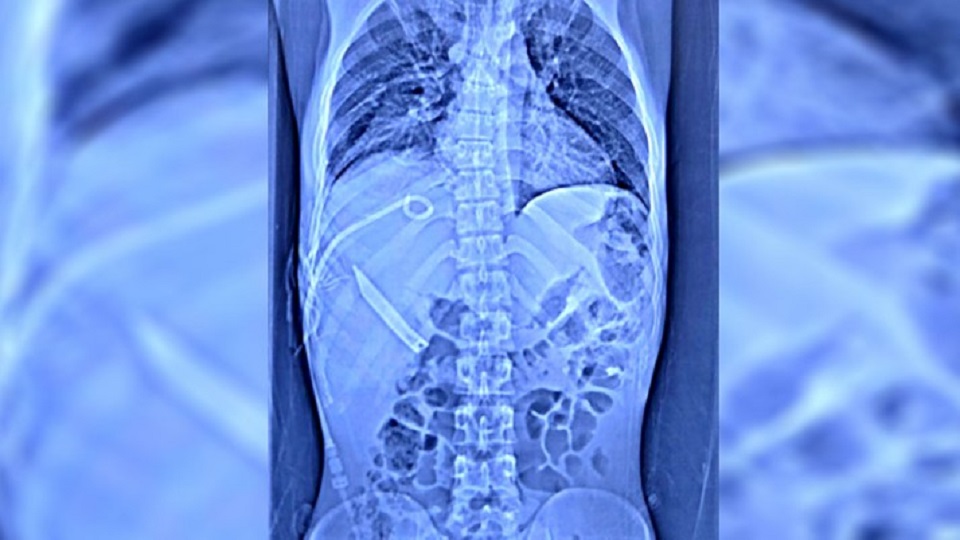

ইচ্ছে হয়েছিল ছুরি চেখে দেখার! তাই প্রায় ২০ সেন্টিমিটার লম্বা একটি ছুরি গিলে ফেলেছিলেন। তারপর বেমালুম ভুলেও গিয়েছিলেন তিনি। পেটে অসহ্য যন্ত্রণা শুরু হতে গেলেন হাসপাতালে। শেষ পর্যন্ত পেট কেটে দিল্লির এমসের চিকিৎসকেরা বের করলেন ওই ছুরিটি। উদ্ধার হওয়া ওই ছুরিটির ধারালো অংশ ১০ সেন্টিমিটার দীর্ঘ। বাকি অংশটি হাতল বলে জানান চিকিৎসকরা।

অপারেশনের দায়িত্বে থাকা এমসের গ্যাস্ট্রো সার্জারি বিভাগের চিকিৎসক এন আর দাশ বলেন, ‘ছুরিটি খাদ্যনালী দিয়ে নীচে নামার সময়ে শ্বাস বা খাদ্যনালীকে চিরে দিতে পারত। এমনকি, ফুসফুস বা হৃদপিণ্ডে ধাক্কা দিতে পারত। ছেলেটির কপাল ভাল যে তেমন কিছু হয়নি। কিন্তু আরও নীচে নেমে তা লিভারে গিয়ে আঘাত করে। ফলে পেটে অসম্ভব ব্যথা শুরু হয়। তার পরেই পেটের এক্সরেতে ছুরি ধরা পড়ে।’

গত ১২ জুলাই দিল্লির সফদরজঙ্গ হাসপাতাল থেকে ওই যুবককে এমসে পাঠানো হয়। এমস সূত্র জানায়, সে সময়ে তার শারীরিক অবস্থা বেশ খারাপ হতে শুরু করেছে। সেপ্টেসেমিয়ার লক্ষণ ধরা পড়তে শুরু করেছে। ফুসফুসে পানি জমে যায়। লিভারে পুঁজ জমতে থাকে। রক্তে হিমোগ্লোবিনের পরিমাণ ছয়ে নেমে আসে। এর মধ্যে ছিল করোনা সংক্রমণের আতঙ্ক। প্রাণ বাঁচাতে অপারেশনের সিদ্ধান্ত নেয়া হয়।’